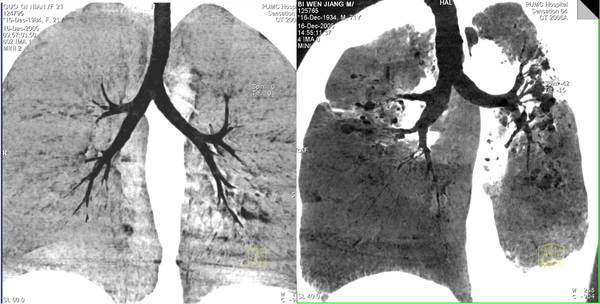

1、MinMIP(最低密度投影)将三维数据向某方向进行投影,取投影线经过的所有体素中最小的一个体素值,作为结果图像的像素值。适用于含气体组织结构和病灶的显示,如气管及支气管显示、消化道充气检查等。它体现了密度信息,但不能测量CT值。